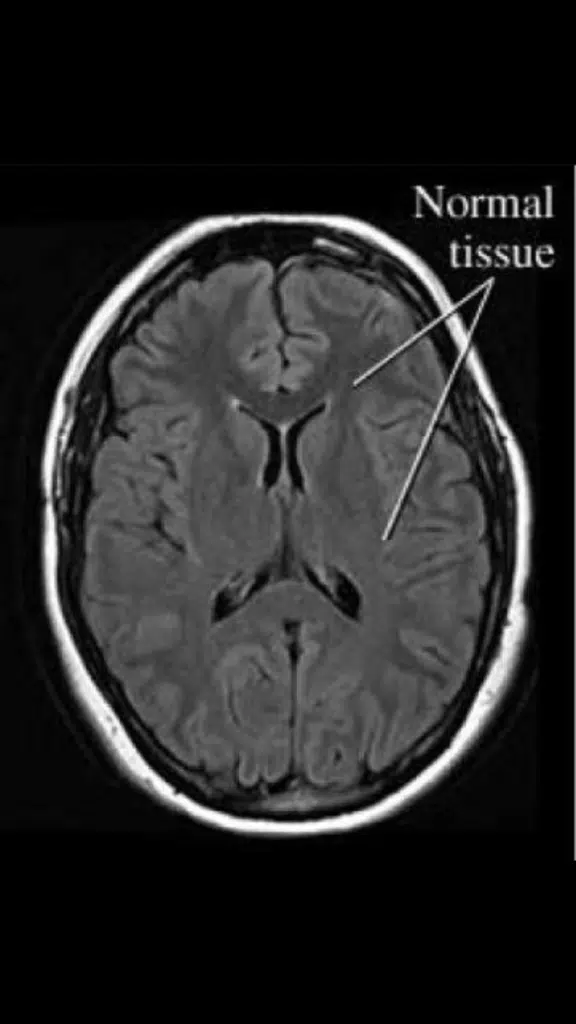

“The first few weeks of Margot’s life back in 2016 were some of the scariest days of our lives,” recalls Erica.  “We immediately fell in love with our little lady when she was born, but we knew within the first hour that something was wrong. An EEG confirmed that she was suffering from seizure activity every 2 seconds. She had low muscle tone and absolutely no hair growth. After an MRI confirmed that she was born with a congenital brain malformation, she was quickly transferred to the NICU at a nearby children’s hospital,” says Erica.

Despite the multiple medications plus alternative therapy that Margot was on for her first several months of life, her EEG confirmed that she was still having constant seizure activity in the back of her brain in both hemispheres. This seizure activity would likely make it difficult for her to process information, ultimately making it difficult for her to have a chance to learn. While her eyes and ears could appear to function normally, her ability to process what she sees and hears would be greatly hindered.  In other words, there wasn’t much more they could do.  It was explained to Erica and Randy that Margot’s condition was incredibly rare to see in infants – that in the 1% of documented epilepsy cases like hers, the babies rarely see the outside of the hospital.  And while this news was scary and a heavy dose of reality for Erica and Randy, their goal was to manage her care at home.